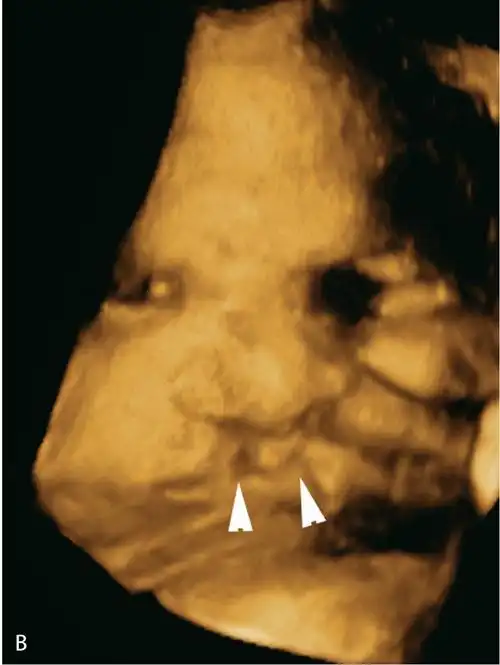

1.3双侧唇裂.(b)同一胎儿的三维图像显示双侧唇裂(三角箭头).图6.1.

1.5正中唇裂.(c,d)三维图像示正中唇裂(箭头)延伸至鼻.